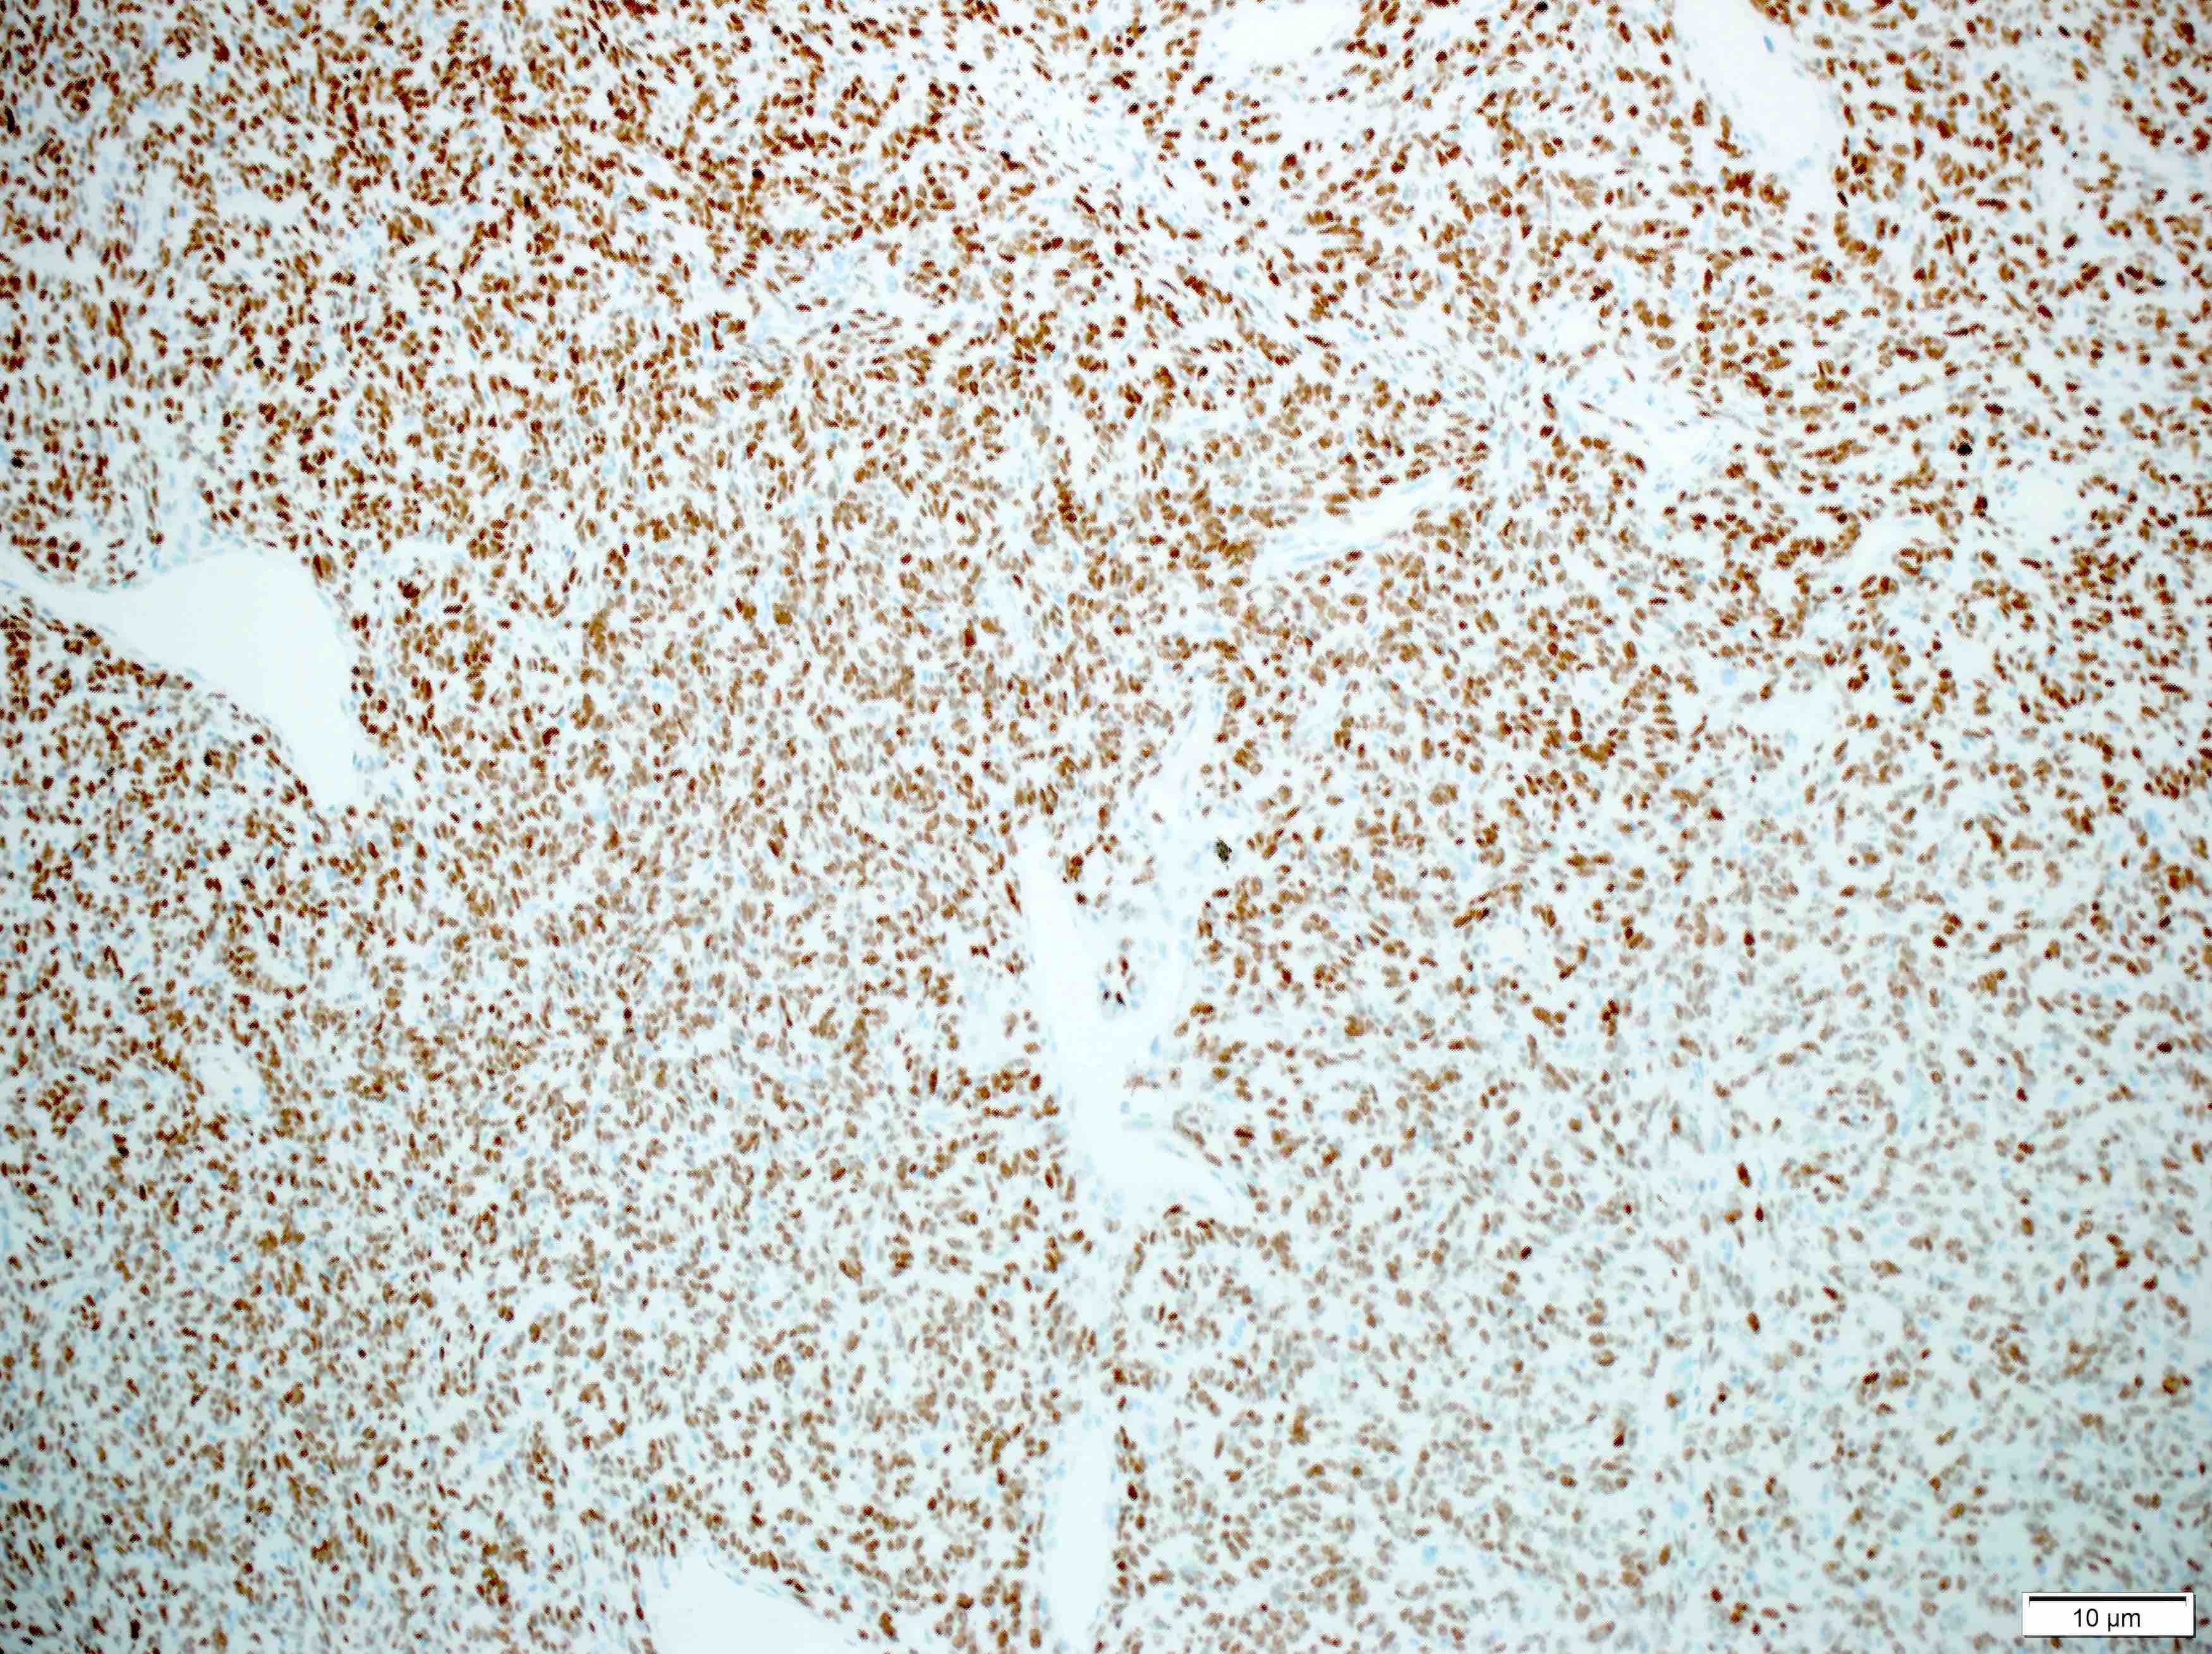

- Positive IHC includes STAT6 (nuclear), CD34 and CD99

Positive stains

- CD34 (lost in some high grade tumors) (Am J Surg Pathol 1997;21:1354)

- STAT6 (nuclear, lost in some dedifferentiated tumors) (Int J Surg Pathol 2017;25:58)

- Vimentin

- CD99

- SMA (tumor periphery)

- BCL2